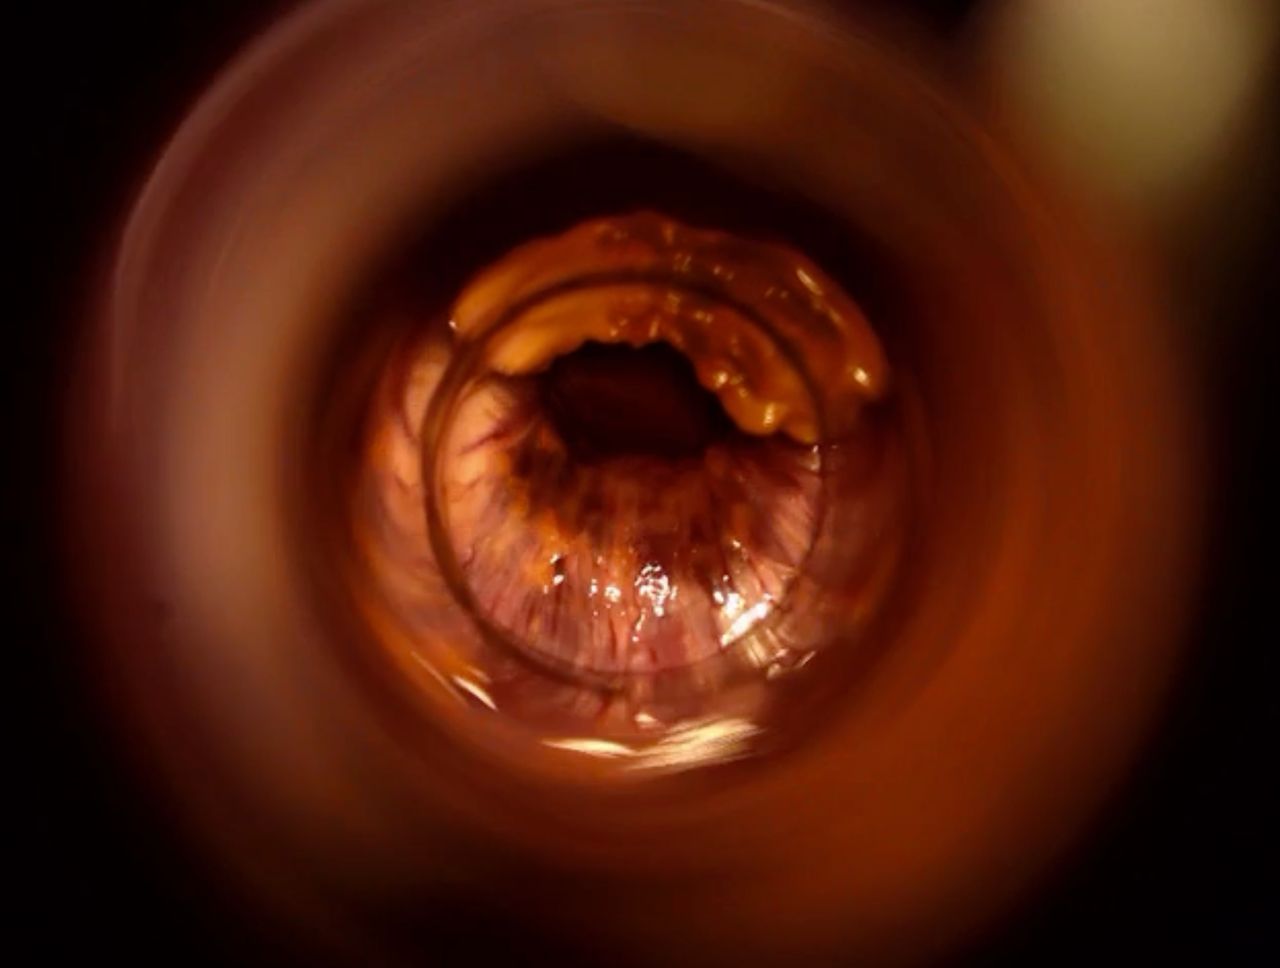

La cura delle emorroidi patologiche, finalmente senza dolore

Come Chirurgo Vascolare, sono perfezionata in Proctologia da molti anni, e molti altri ne ho passati direttamente in sala operatoria, praticando l'emorroidectomia con metodo Milligan-Morgan.

Durante la mia esperienza come Chirurgo Protcologo, ho visto personalmente come i trattamenti chirurgici disponibili, benché necessari, fossero comunque abbastanza invasivi per il paziente, specialmente nel decorso post operatorio.

Fortunatamente, negli ultimi anni sono stati messi a punto protocolli non chirurgici molto avanzati, che ho personalmente studiato ed approfondito con molto interesse.

Tra questi, ho cominciato ad utilizzare il trattamento sclerotizzante con scleromousse stabilizzata ad aria sterilizzata, che considero ormai il 'Gold Standard' per il trattamento non invasivo e permanente delle emorroidi patologiche.

Ho quindi attrezzato il mio studio con il moderno Videoproctoscopio Digitale, nonché con avanzate pompe miscelatrici ad aria sterilizzata, in grado di ottenere una scleromousse stabilizzata di grande qualità, perfetta per il trattamento emorroidale.

Grazie a questo protocollo, posso risolvere casi anche molto gravi di prolasso emorroidale, garantendo una risoluzione definitiva in oltre il 95% dei casi clinici.

Il tutto, senza il minimo dolore o disagio per il paziente.